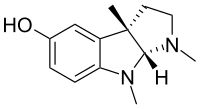

Indoles

- 18-Methoxycoronaridine

- 7-Acetoxymitragynine

- 7-Hydroxymitragynine

- ψ-Akuammigine

- Akuammidine

- Akuammine

- Coronaridine

- Eseroline

- Hodgkinsine

- Ibogaine

- Mitragynine

- Mitragynine pseudoindoxyl

- Noribogaine

- Pericine

- Pseudoakuammigine

Structures

| Indoles | ||||

|---|---|---|---|---|

|

7-Acetoxymitragynine |

|

Akuammidine |

|

|

|

-Mitragynine_Structural_Formula_V1.svg.png.webp)

|

|

|